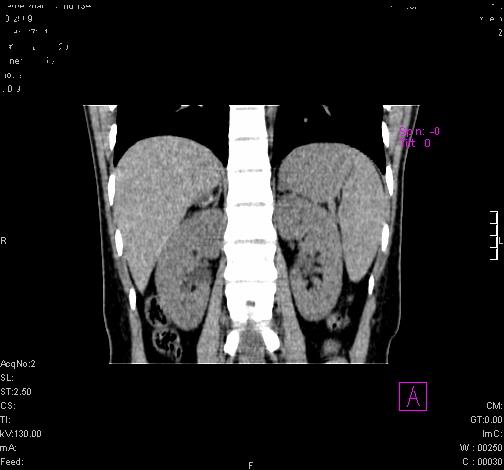

患者为年轻女性,查体发现右侧肾上腺囊性占位。无临床体征。

这么漂亮的图像,一看一目了然。典型的右侧肾上腺囊肿,周围有钙化。感谢搂主!

“肾上腺囊肿组织学分为4类:1)内皮细胞性,2)假性囊肿,3)寄生虫性,4)上皮细胞性。其中内皮细胞性最为常见。假性囊肿多为肾上腺内出血后遗留囊腔,囊壁无上皮细胞。寄生虫性多为包虫病引起。上皮性则很少见。”

这么明显的弧形钙化,多考虑包虫病所致的寄生虫性囊肿。

右侧肾上腺囊性密度灶囊壁有钙化。考虑肾上腺囊肿,结核?

右侧肾上腺囊肿,周围有钙化。